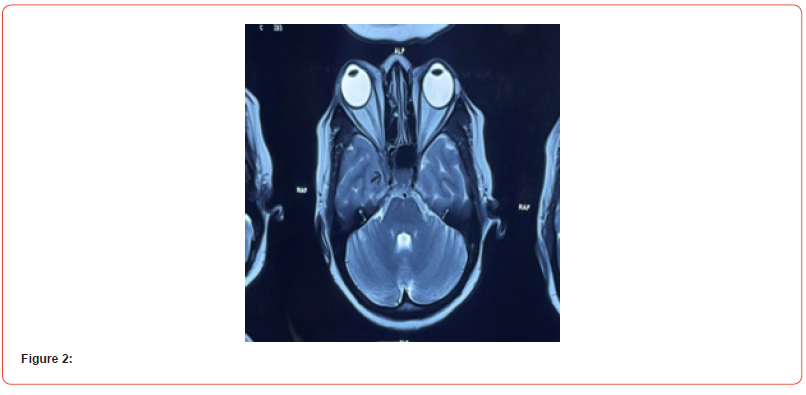

Her initial laboratory tests showed white blood cell count, 9.400/ml; red blood cell count, 4.56×10/μl; hemoglobin, 13.1 g/ dl; platelets 183×103; ESR 89 mm in 1st hour. Glucose, 82 mg/dl, blood urea nitrogen, 10 mg/dl; creatinine, 0.83 mg/dl; ELISA for HIV, negative; D-Dimer, 351 ng/ml (<500 ng/ml). Thyroid function tests showed TSH, 1.81 μUI/ml (0.34-5.60); free T3, 3.64 pg/ml (2.50 - 3.90); free T4, 0.96 ng/ dl (0,54-1.64). The cerebral spinal fluid reported 4 mononuclear cell/uL; glucose, 69 mg/dl; proteins, 55 mg/dl; ADA and PCR in CFS for tuberculosis were negative. ANA was positive in cytoplasmic pattern 1:40; anti-ds DNA, ENA profile, c-ANCA and p-ANCA were negative. CT scan of brain and paranasal sinus, MRV and MRA of the brain were normal (figure 3). (SOV) thrombosis was seen. MRI of brain with orbit with contrast was done in multiple axial, coronal and sagittal sections which showed iso to hypo-intense lesion in right cavernous sinus extending up to right superior orbital fissure (figure 2). The lesion was brilliantly contrast enhancing and causing significant compression of the neurovascular structure of right cavernous sinus. Both optic nerves were spared. ICA was also normal in diameter (Figure 2 & 3).

Figure 2 and figure 3 showing Axial MRI Brain T1W image reveals intense enhancement of the soft-tissue mass within the right cavernous sinus (black arrow) and normal MRA of brain respectively. Since the studies showed no abnormalities and we excluded neoplasic, infectious, vascular, thyroid and metabolic causes of painful ophthalmoplegia, we decided to start treatment for Tolosa- Hunt Syndrome with metilprednisolne 1 gr IV daily for 3 days, and noticed significant response of the right periorbital pain, palpebral ptosis and the ipsilateral ocular motor nerve palsies in next 2 weeks. At day 4, we changed treatment to prednisone at 1 mg/kg daily. Two weeks later, we initiated steroid tapering every week, and at week 12 the patient was asymptomatic and her neuro- ophthalmologic examination was completely normal.(Figure 4). The probable diagnosis of Tolosa–Hunt Syndrome was retained in the face of the negativity of all investigations carried out as well as spectacular response to treatment (Figure 4).

With careful clinical examination, pain associated with typical cranial nerve palsies localizes the pathological process to the regions of the cavernous sinus/superior orbital fissure. As noted above, current neuroimaging modalities allow visualization of the area of suspected pathology. Contrast enhanced MRI with multiple views, particularly coronal sections, should be the initial diagnostic study performed. Numerous reports have demonstrated an area of abnormal soft tissue in the region of the cavernous sinus in most, but not all, patients with Tolosa-Hunt syndrome [14,24,25,26,27]. Typically, the abnormality is seen as an intermediate signal intensity on T1 and intermediate weighted images, consistent with an inflammatory process. In addition, there is enhancement of the abnormal area after intravenous injection of paramagnetic contrast. With corticosteroid therapy, the abnormal area decreases in volume and signal intensity in most reported cases.

The major limitation of MRI findings in Tolosa-Hunt syndrome is their lack of specificity. Thus, Yousem et al 24 examined 11 patients and reported pathological MRI findings in the cavernous sinus in nine. In six of these nine the affected cavernous sinus was enlarged; in five of nine it had a convex lateral wall. Extension into the orbital apex was seen in eight patients. Yet the signal characteristics (hypointense relative to fat and isointense with muscle on T1 weighted images; isointense with fat on T2 weighted scans) were also consistent with meningioma, lymphoma, and sarcoidosis. Some authors reported that using carotid angiography there was segmental narrowing of the carotid siphon was seen [28].